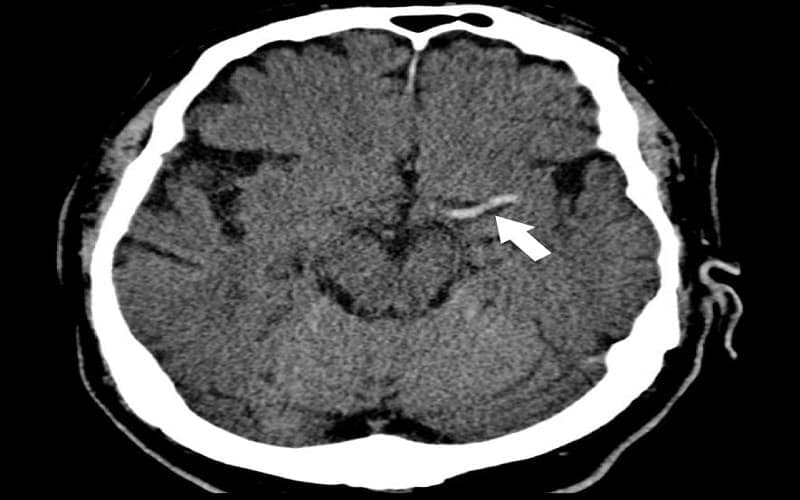

2.5. Dấu hiệu tăng đậm động mạch (hyperdense artery sign)

Dấu hiệu này biểu hiện bằng hình ảnh động mạch tăng tỷ trọng bất thường do có cục máu đông trong lòng mạch. Thường gặp ở động mạch não giữa, đây là dấu hiệu trực tiếp cho thấy tắc mạch trên chụp CT nhồi máu não, có giá trị cao trong chẩn đoán sớm.